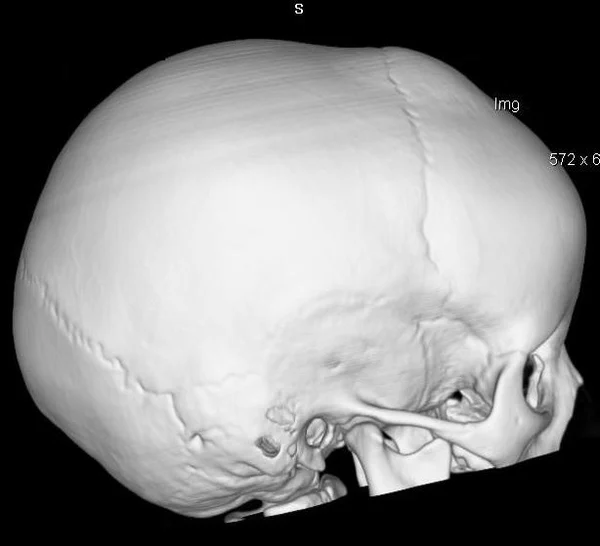

Удаление опухолей черепаВ качестве примера лечения пациентов с опухолями черепа привожу личное наблюдение пациента грудного возраста с опухолью черепа. В возрасте 1 мес. у ребёнка в затылочной области слева родителями обнаружено плотное образование диаметром 5 мм. За 3 мес. до госпитализации образование значительно увеличилось в размерах. При поступлении в возрасте 6 мес. в затылочной области слева (в проекции лямбдовидного шва) имеется безболезненное, плотное, неподвижное, бугристое образование размерами 5 х 4 х 2 см. При КТ и МРТ головы выявлена опухоль черепа в области астериона слева, обладающая преимущественно интракраниальным ростом (рис. 30 а). Ребёнку выполнено удаление опухоли черепа (рис. 30 б). Образовавшийся дефект черепа больших размеров закрыт перфорированной титановой пластиной (рис. 30 в). При наблюдении пациента в течении 2-х лет рецидива заболевания и деформации черепа не отмечалось.